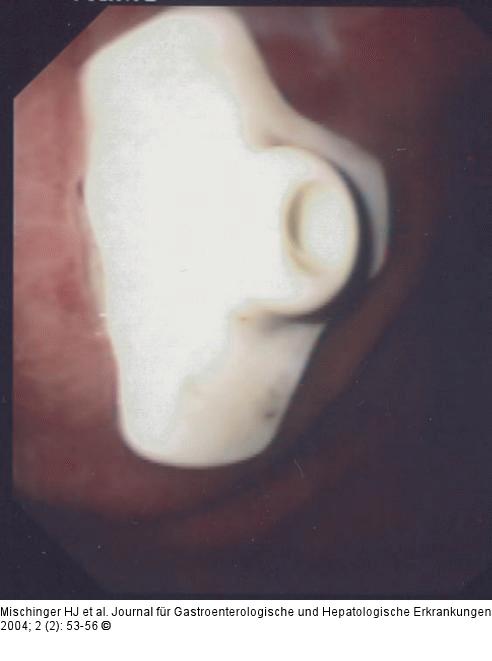

Abbildung 12: PEG - Technik

Am Faden wird solange gezogen, bis das Widerlager an der Magenvorderwand zu liegen kommt. |